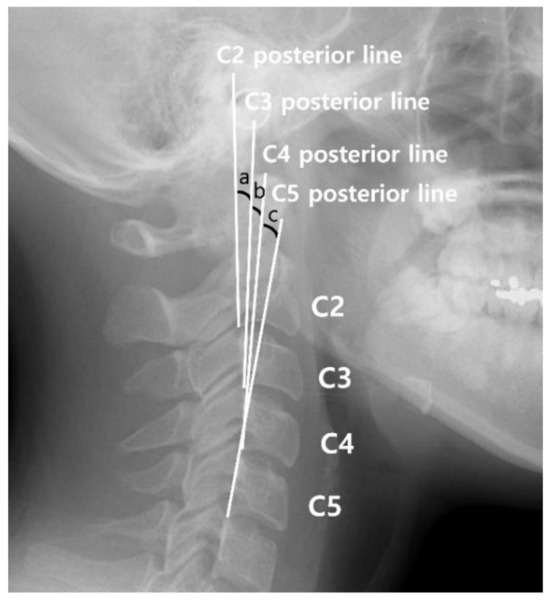

- C2–C5 Harrison posterior tangent method (Figure 4) [28]: The lines are drawn parallel to the posterior surface of each cervical vertebral body from C2 to C5, and angles from C2 to C3, C3 to the fourth cervical vertebra (C4), and C4 to C5 is added. When the posterior surface line of the lower vertebral body opens more clockwise than the upper vertebral body, the angle is considered positive. In this study, if the summed angle was >10° but <30°, it was classified as a ‘lordotic.’ If the summed angle was <10° but >−5°, it was classified as ‘straight.’ If the summed angle was <−5°, it was classified as ‘kyphotic’. Because this study analyzed data from the middle of C6 to the upper part of the cervical vertebral bodies, measurements were extended only up to C5 in this method.